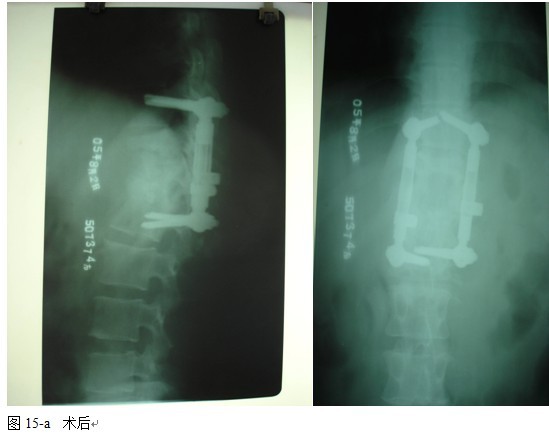

结果: 术后所有患者均显示,骨性融合, 马尾神经损伤的患者均基本恢复正常,术后后凸畸形平均矫正90%以上, 3-49个月的随访,后凸角度平均丢失4.2°。

结论: 后路椎弓根系统内固定加前后路植骨融合能加强脊柱的稳定性, 促进骨融合和神经的恢复, 畸形矫整明显。

本组手术用时间3~4h , 平均3.5h 。术中出血300~500ml , 平均约350ml 。术后症状完全缓解,无神经功能障碍加重等并发症,1例营养差的老年患者伤口出现窦道,1例因肝功能差,术后未口服抗痨药,伤口出现窦道,经换药后二期愈合,其余病例伤口均一期愈合。马尾神经受损的患者术后基本恢复正常。术后一周后凸角平均 5.4°后凸畸形平均矫正90%以上, 最终后凸角平均8.3°,后凸角度平均丢失4.2°。随访3个月有87%(40/46)有骨痂形成,6个月91.3%(42/46)明显骨性愈合(见图),其余4例9-12个月内愈合,随访时间3-32个月,平均11个月,46例患者中2例在术后2个月和3个月时背部形成脓肿,换药后治愈。2例出院1月后并发结核性脑膜炎,治疗后好转。1例因椎弓根钉偏外,刺激神经根,5个月后从侧方脱出,疼痛加重,因前后路植骨完全愈合,取出后症状完全缓解。

中国学者金大地[22]等采用一期前路病灶清除植骨前路钢板固定治疗腰椎结核,平均18°的后凸畸形得以矫正,Mukhtar[23] AM等采用前路病灶清除植骨分期或同期后路固定治疗腰椎结核22例,术后后凸畸形矫正度数平均为27°。从我们的随访结果看,术后后凸畸形平均矫正度数为26.9°,后凸畸形平均矫正90%以上, 6个月-49个月后随访,后凸角度平均丢失4.2°。本术式也适用于结核所引起的弹性差的后凸畸形,对于病灶纤维化或骨化的非弹性后凸畸形,后路固定后,先行前路病灶、纤维化或骨化切除、松解,逐步刮除病灶、逐步撑开,达到畸形矫正和植骨的目的。